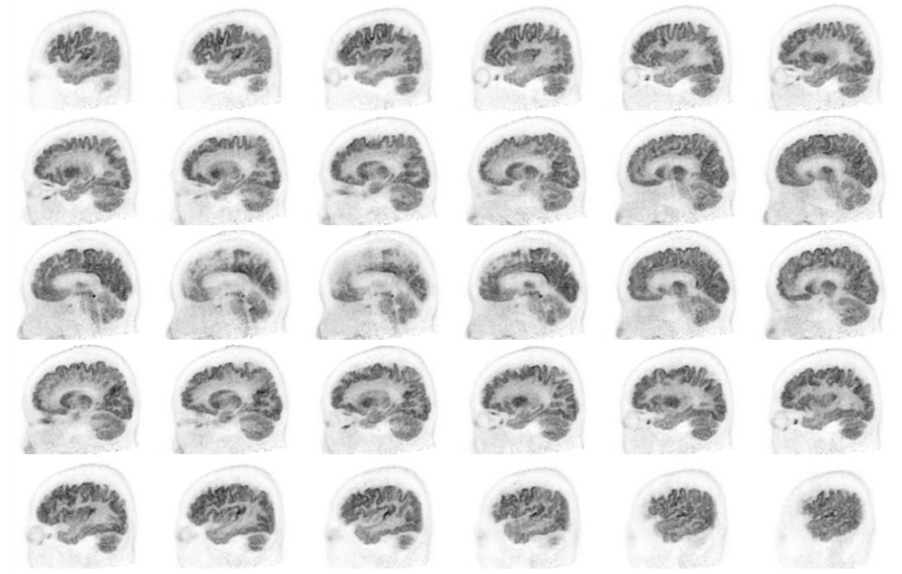

Head / Case3 : FDG

Sagittal

Courtesy : Kindai University Hospital

- Imaging protocol

- Injected dose: 4.49 MBq/kg, 18F-FDG

- Uptake time: 46 minutes

- Scan time: 30 minutes